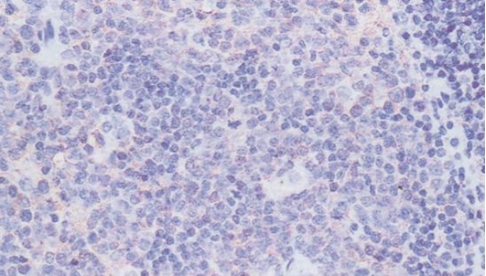

CD45 staining of paraffin-embedded human lymph node sections: Due to insufficient tissue fixation, lymphocytes at the edge of the lymph node show strong CD45 positivity, while those in the inner part of the tissue exhibit weak positivity, leading to uneven staining overall.